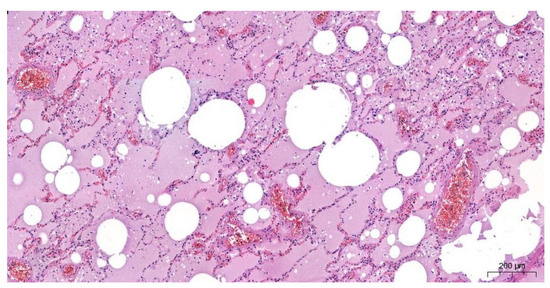

2.2.3. The Microscopic Examinations